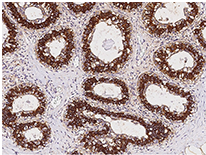

Anti-FASN Ab, Rabbit pAb: (Cat#: 100685-T10)

Immunochemical staining of human FASN in the human breast. Image Credit: Sino Biological Inc.

- Applications: IHC-P, ICC/IF